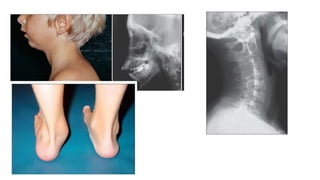

X ray finding

• Soft tissue swelling

• Osteoporosis

• Joint space narrowing , carpal crowding

• Erosion and ankylosis

• Epiphyseal compression

• Periosteitis

Disability and deformity

• Deformity – Knee ( leg length disparity ,valgus ) , ankle ( valgus ) , cervical spine

abnormality , altered craniofacial profile due to TMJ arthritis